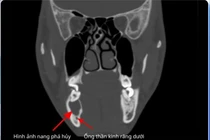

Hình thành u nang hoặc tổn thương xương hàm: Một số răng khôn mọc bất thường có thể tạo u nang quanh thân răng, làm tiêu xương và ảnh hưởng các răng lân cận.

Nang xương hàm có thể làm phá hủy xương, tiêu chân răng lân cận, ảnh hưởng tới mầm răng vĩnh viễn, mất thẩm mỹ và gây đau đớn, sưng viêm khi nang bội nhiễm.

Chỉ vì chủ quan với một chiếc răng sâu, anh N. (25 tuổi) đã đối mặt biến chứng nặng, nhiễm trùng lan rộng tạo nang xương hàm, buộc phải nhổ bỏ cùng lúc 3 răng để xử lý ổ viêm.